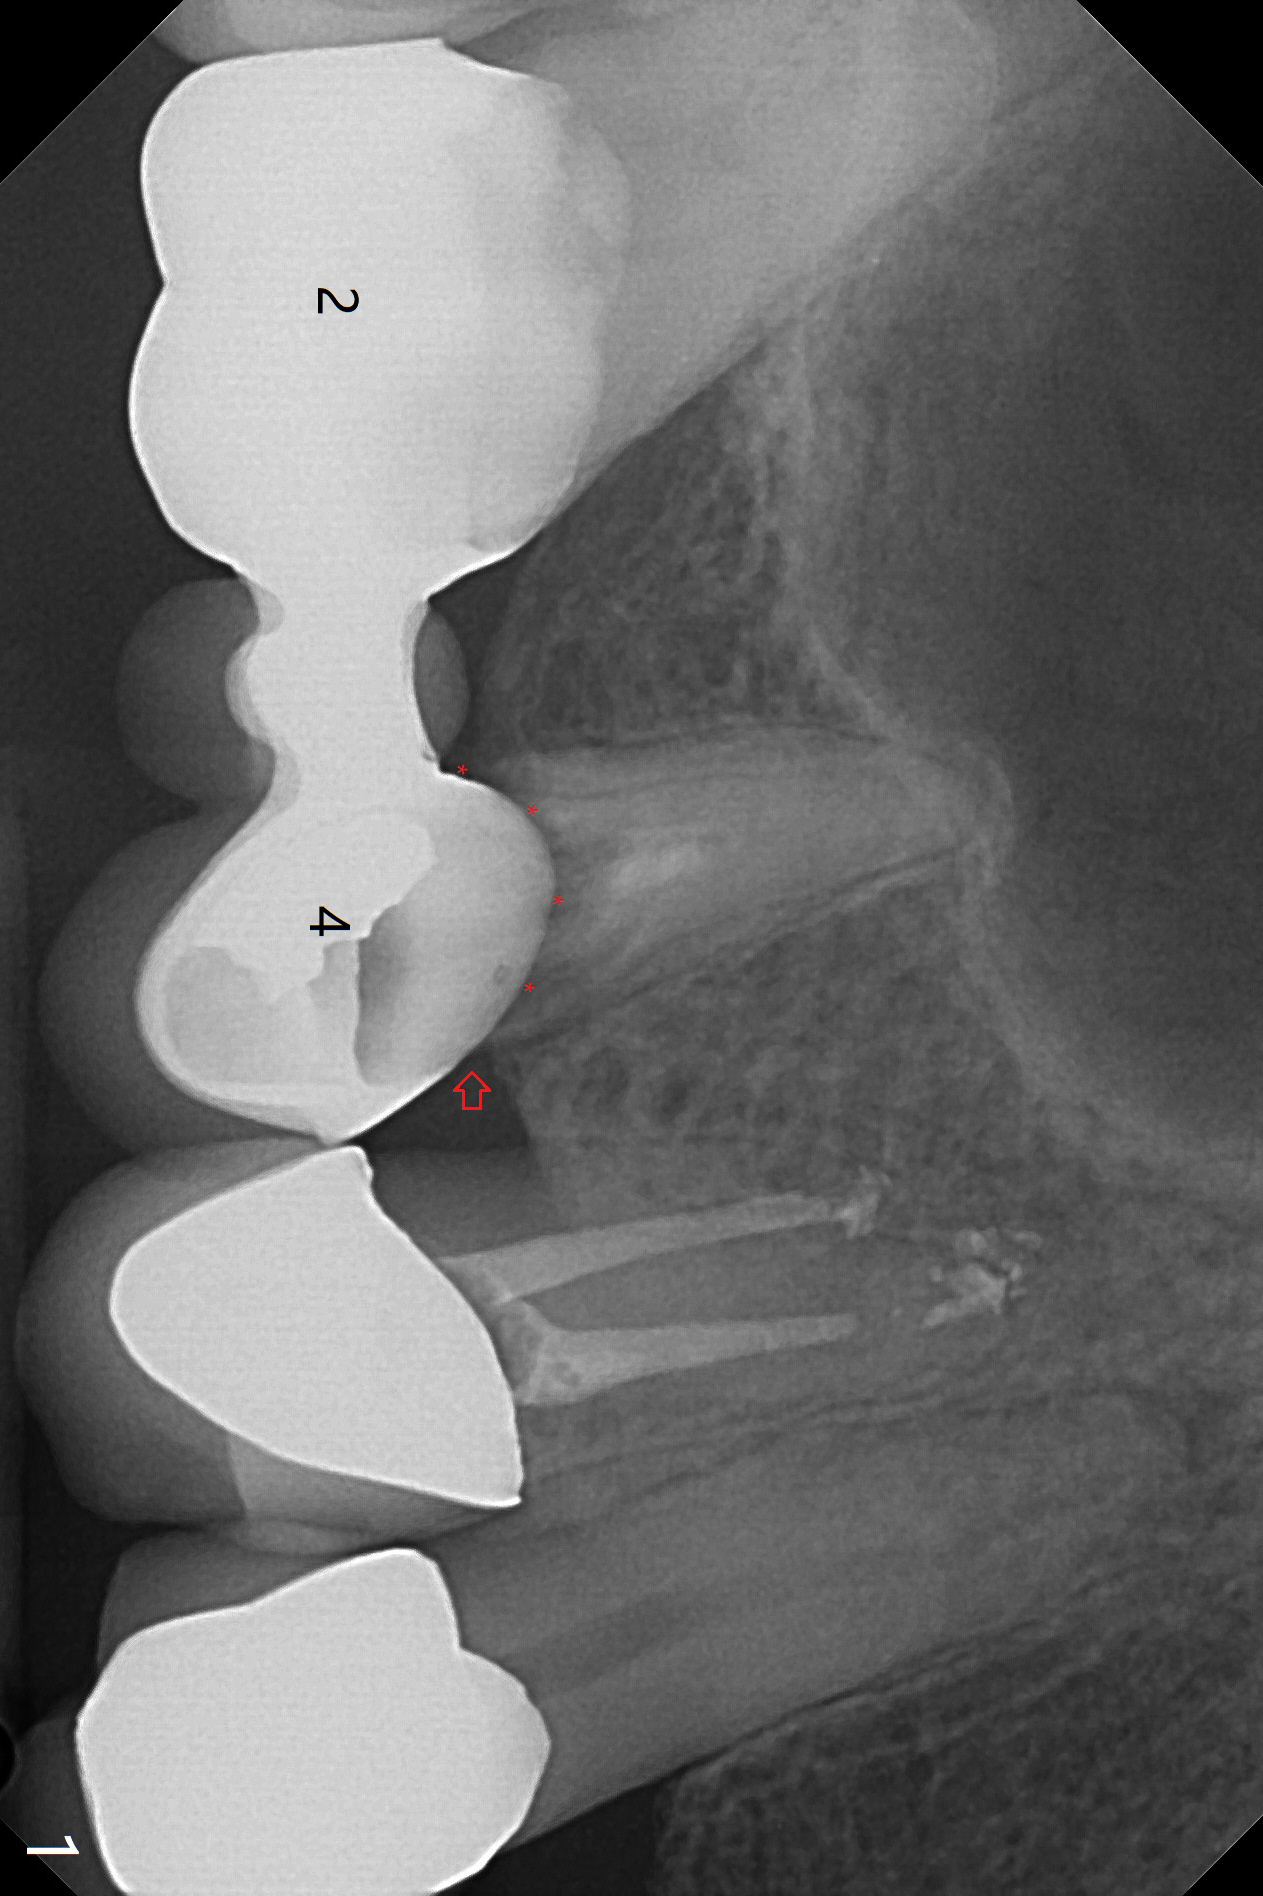

A 56-year-old man complains of food impaction under UR FPD (fixed partial denture, bridge).  Floss goes through between #4 abutment and retainer (Fig.1 red arrow and *).